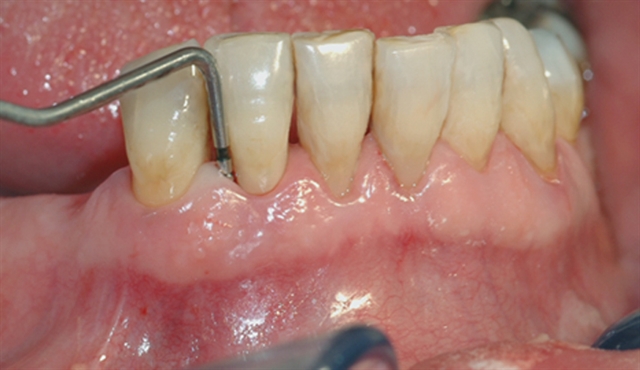

• perio stor 3

perio stor 3

Instrumentet er her lagt utenfor tannkjøttet for å vise hvor stort festetapet egentlig er.